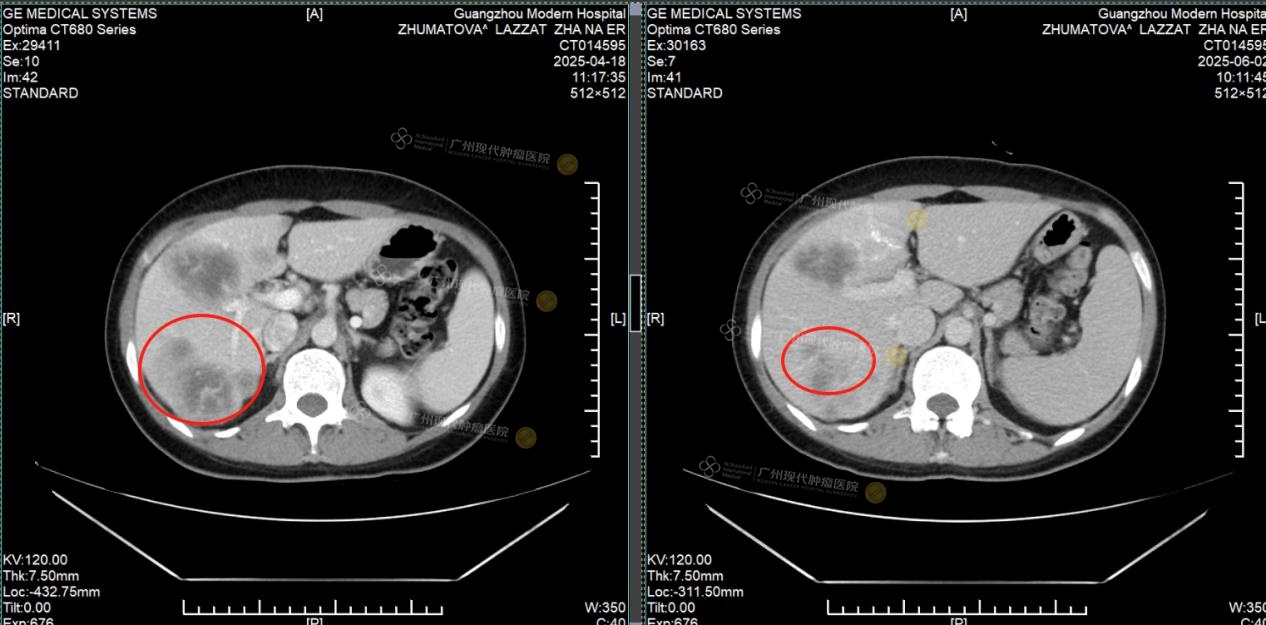

Pada April 2025, Lazzat datang ke rumah sakit kami ditemani oleh kakaknya dan menjalani pemeriksaan menyeluruh. Hasil CT menunjukkan bahwa terdapat massa tumor pada payudara kiri dengan ukuran sekitar 2×1cm, serta banyak lesi metastasis di hati, dengan diameter nodul terbesar lebih dari 4cm. Fungsi hati juga telah terpengaruh oleh tumor.

Lesi metastasis hati: sebelum pengobatan vs sesudah pengobatan, sebagian besar tumor sudah hilang

Setelah menjalani 2 siklus pengobatan, tumor payudara Lazzat berhasil dihilangkan sepenuhnya dan tidak terdeteksi lagi saat pemeriksaan ulang. Lesi metastasis di hati menyusut lebih dari setengah, fungsi hati kembali normal, dan penanda tumor seperti CEA dan CA153 menunjukkan penurunan yang signifikan. Berkat perawatan yang cermat dari tenaga medis, fungsi hatinya membaik, rasa lelah dan lemas pun berkurang secara nyata, dan ia kembali merasakan semangat hidup yang sudah lama hilang.